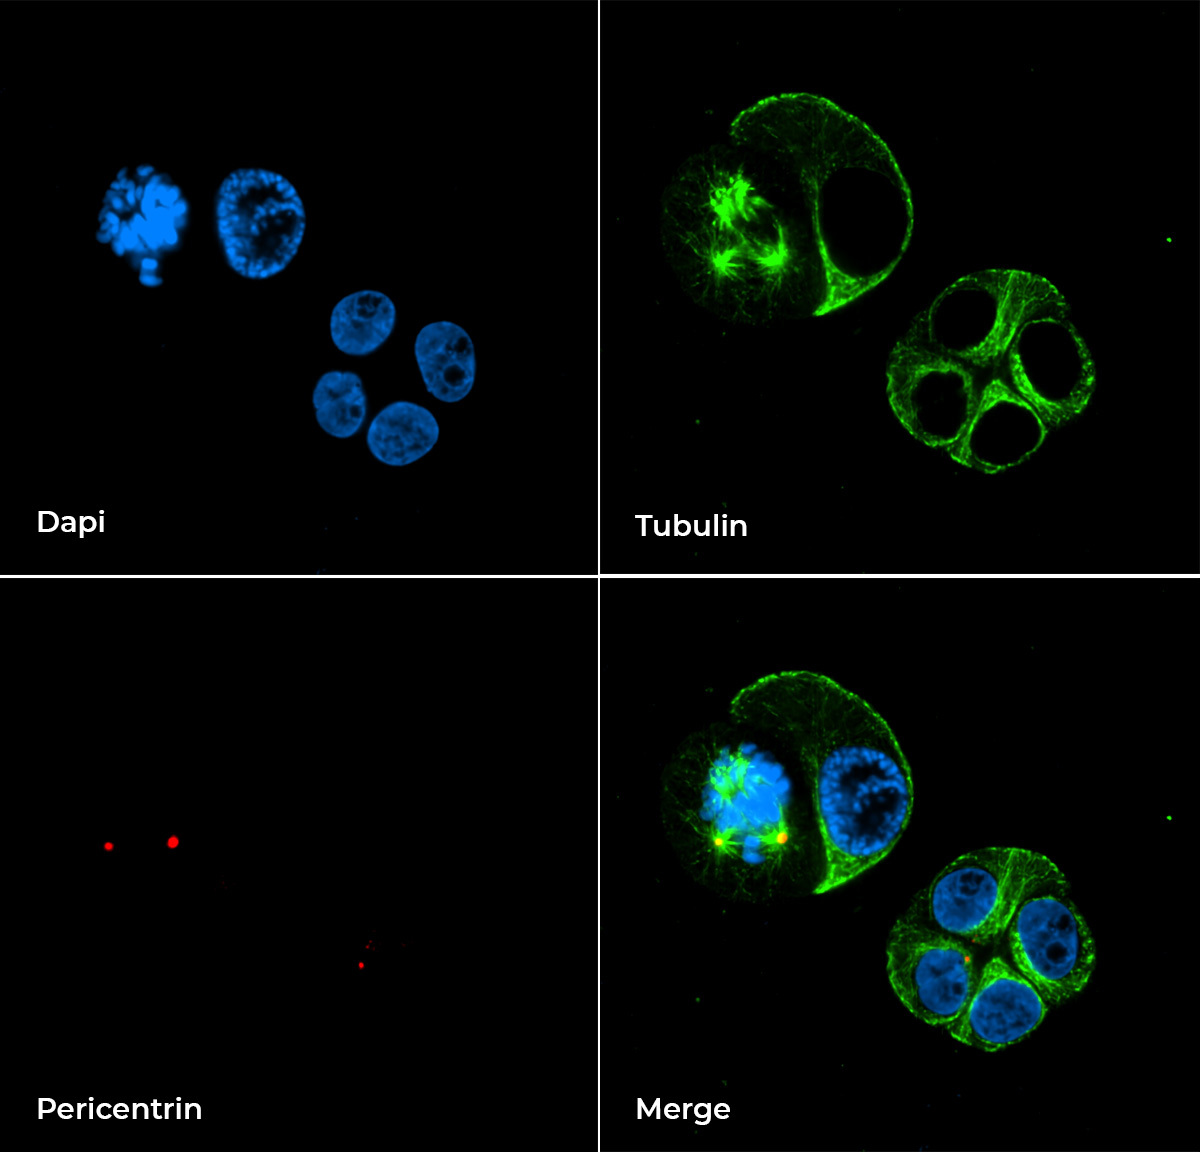

Figure 2 shows two representative early stages (three days in vitro, DIV 3) non-malignant acini grown in 3D Matrigel suspensions. Tubulin (green) identifies the skeleton and therefore the structure of the spheroid, while pericentrin (red) identifies the correct orientation of the mitotic spindle and, therefore, the symmetry of cell divisions within the spheroid.

A

B

Figure 2: Example of a typical non-malignant acinar structure cross-section (A). 3D volume view of a typical non-malignant acini (B). Cells were cultured in 3D Matrigel suspensions and stained with tubulin (green), pericentrin (red) and DAPI (blue). These images were acquired with a CFI Plan Apochromat Lambda D 60x oil objective (60x, Nikon, 1.42 NA and 0.15 mm WD).